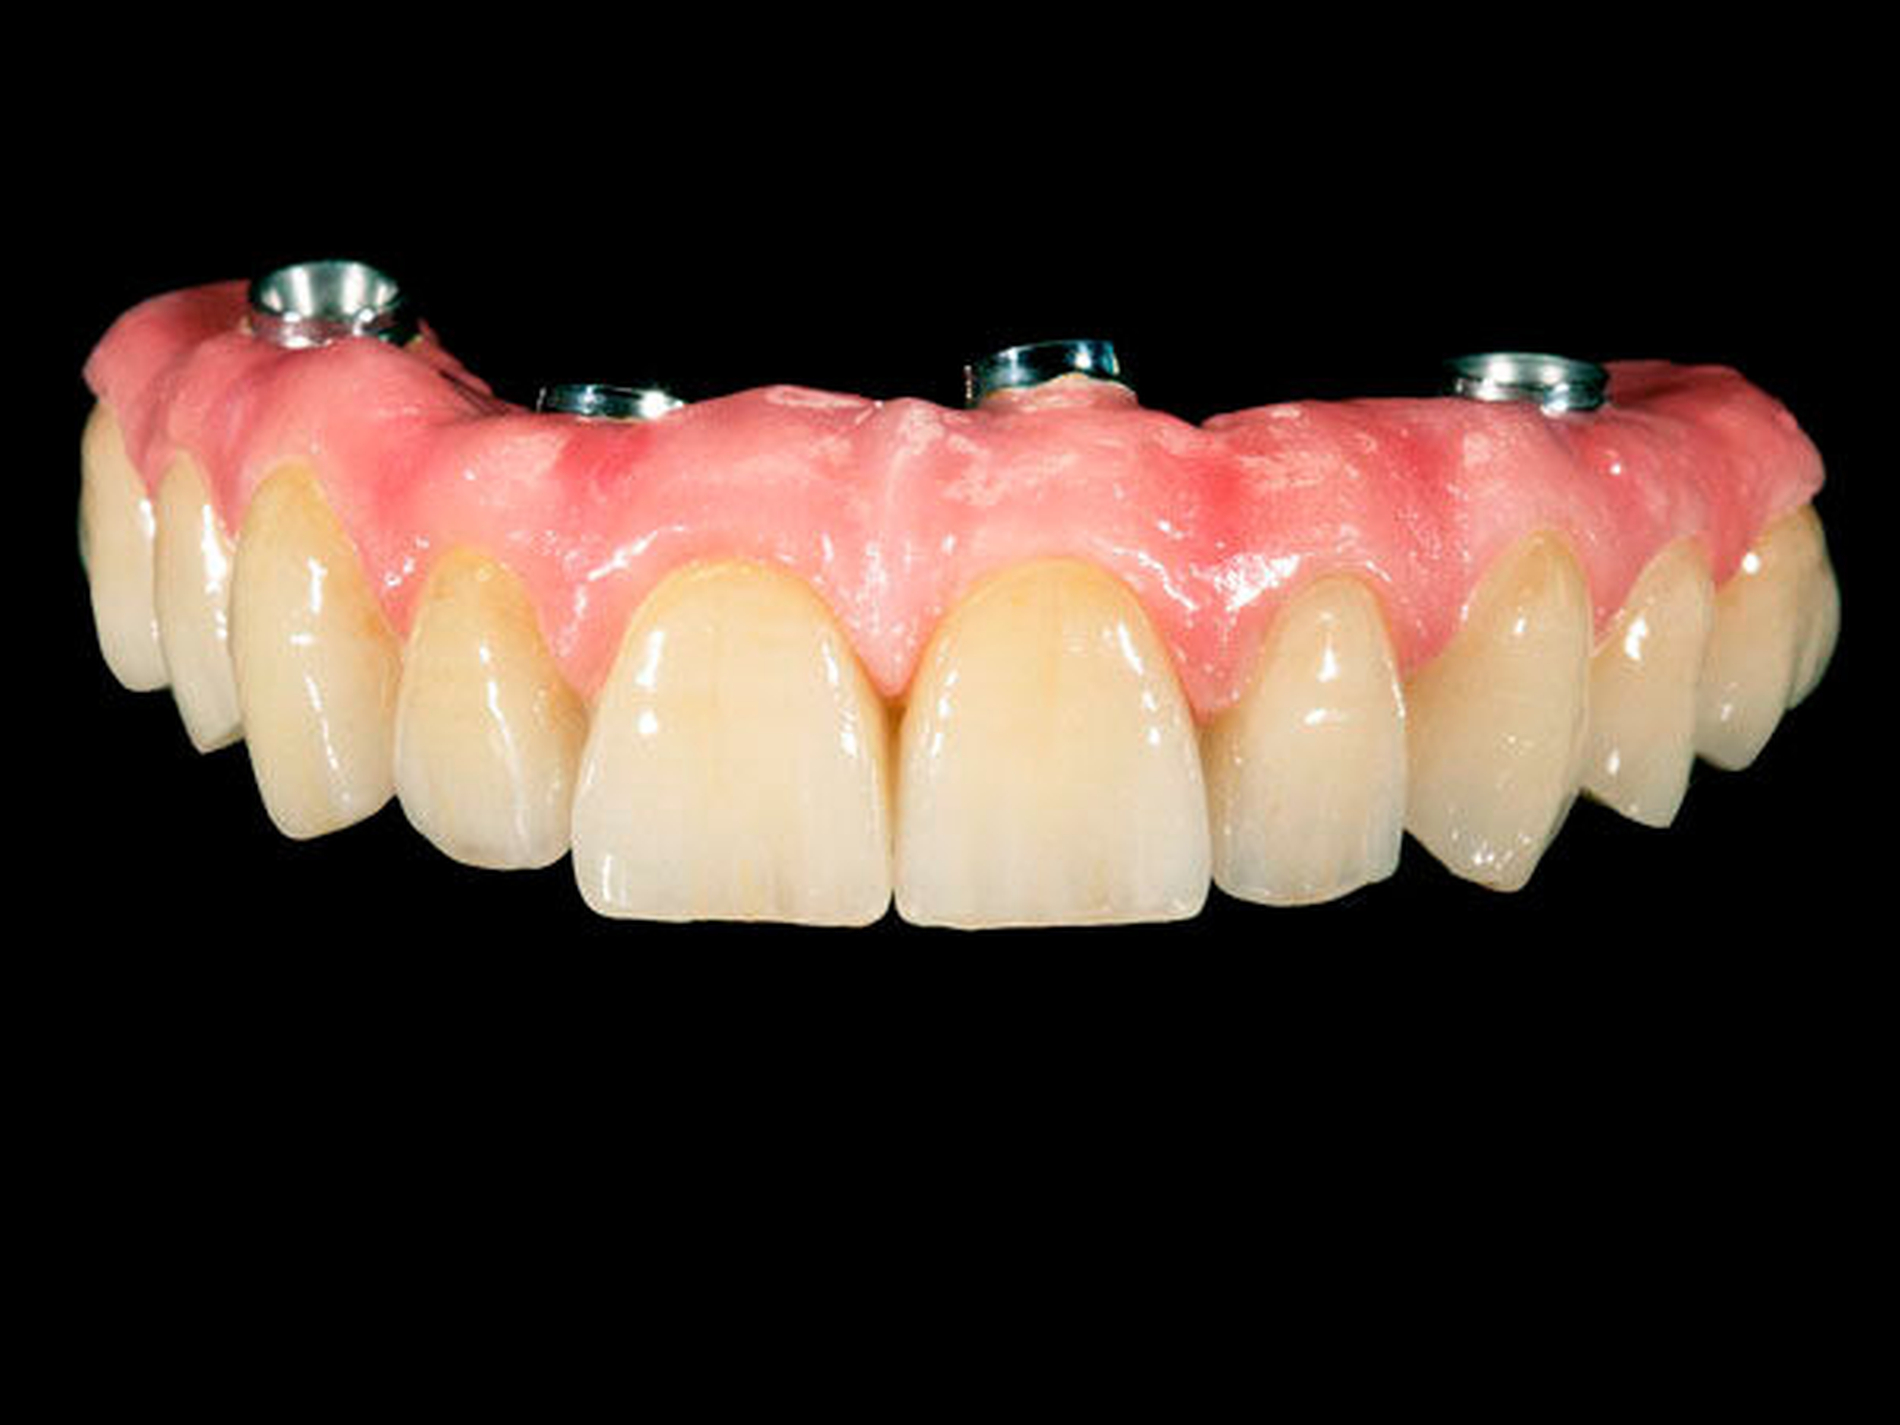

Um die Belastung der distalen Implantate nicht zu erhöhen, wird die Sofortversorgung ohne Freienden hergestellt und hat typischerweise zehn ersetzte Zähne. Auf eine Metallbasis wird bewusst verzichtet, um bei einer eventuellen Überbelastung durch einen vorzeitigen Bruch des Prothesenkunststoffs (quasi als Sollbruchstelle) die Belastung von den Implantaten fernzuhalten. Die Basis soll darüber hinaus hygienefähig, das heißt, gerade oder konvex gestaltet und hochglanzpoliert sein. Eine gleichmäßige Okklusion ohne Frühkontakte ist im Hinblick auf die Reduktion des Frakturrisikos und die Vermeidung einer Überbelastung der Implantate wichtig.

2. Phase: Gemäß unserem Protokoll wird nach frühestens sechs Monaten eine definitive Versorgung hergestellt, die mit einem im CAD/CAM-Verfahren hergestellten Titangerüst verstärkt ist und durch beidseitige Freienden typischerweise zwölf Zähne ersetzt. Hier gibt es die Möglichkeit zur Herstellung einer Brücke mit aufgestellten Kunststoffzähnen (Abbildung 3) oder individuell hergestellten, keramischen Einzelkronen (Abbildung 4).